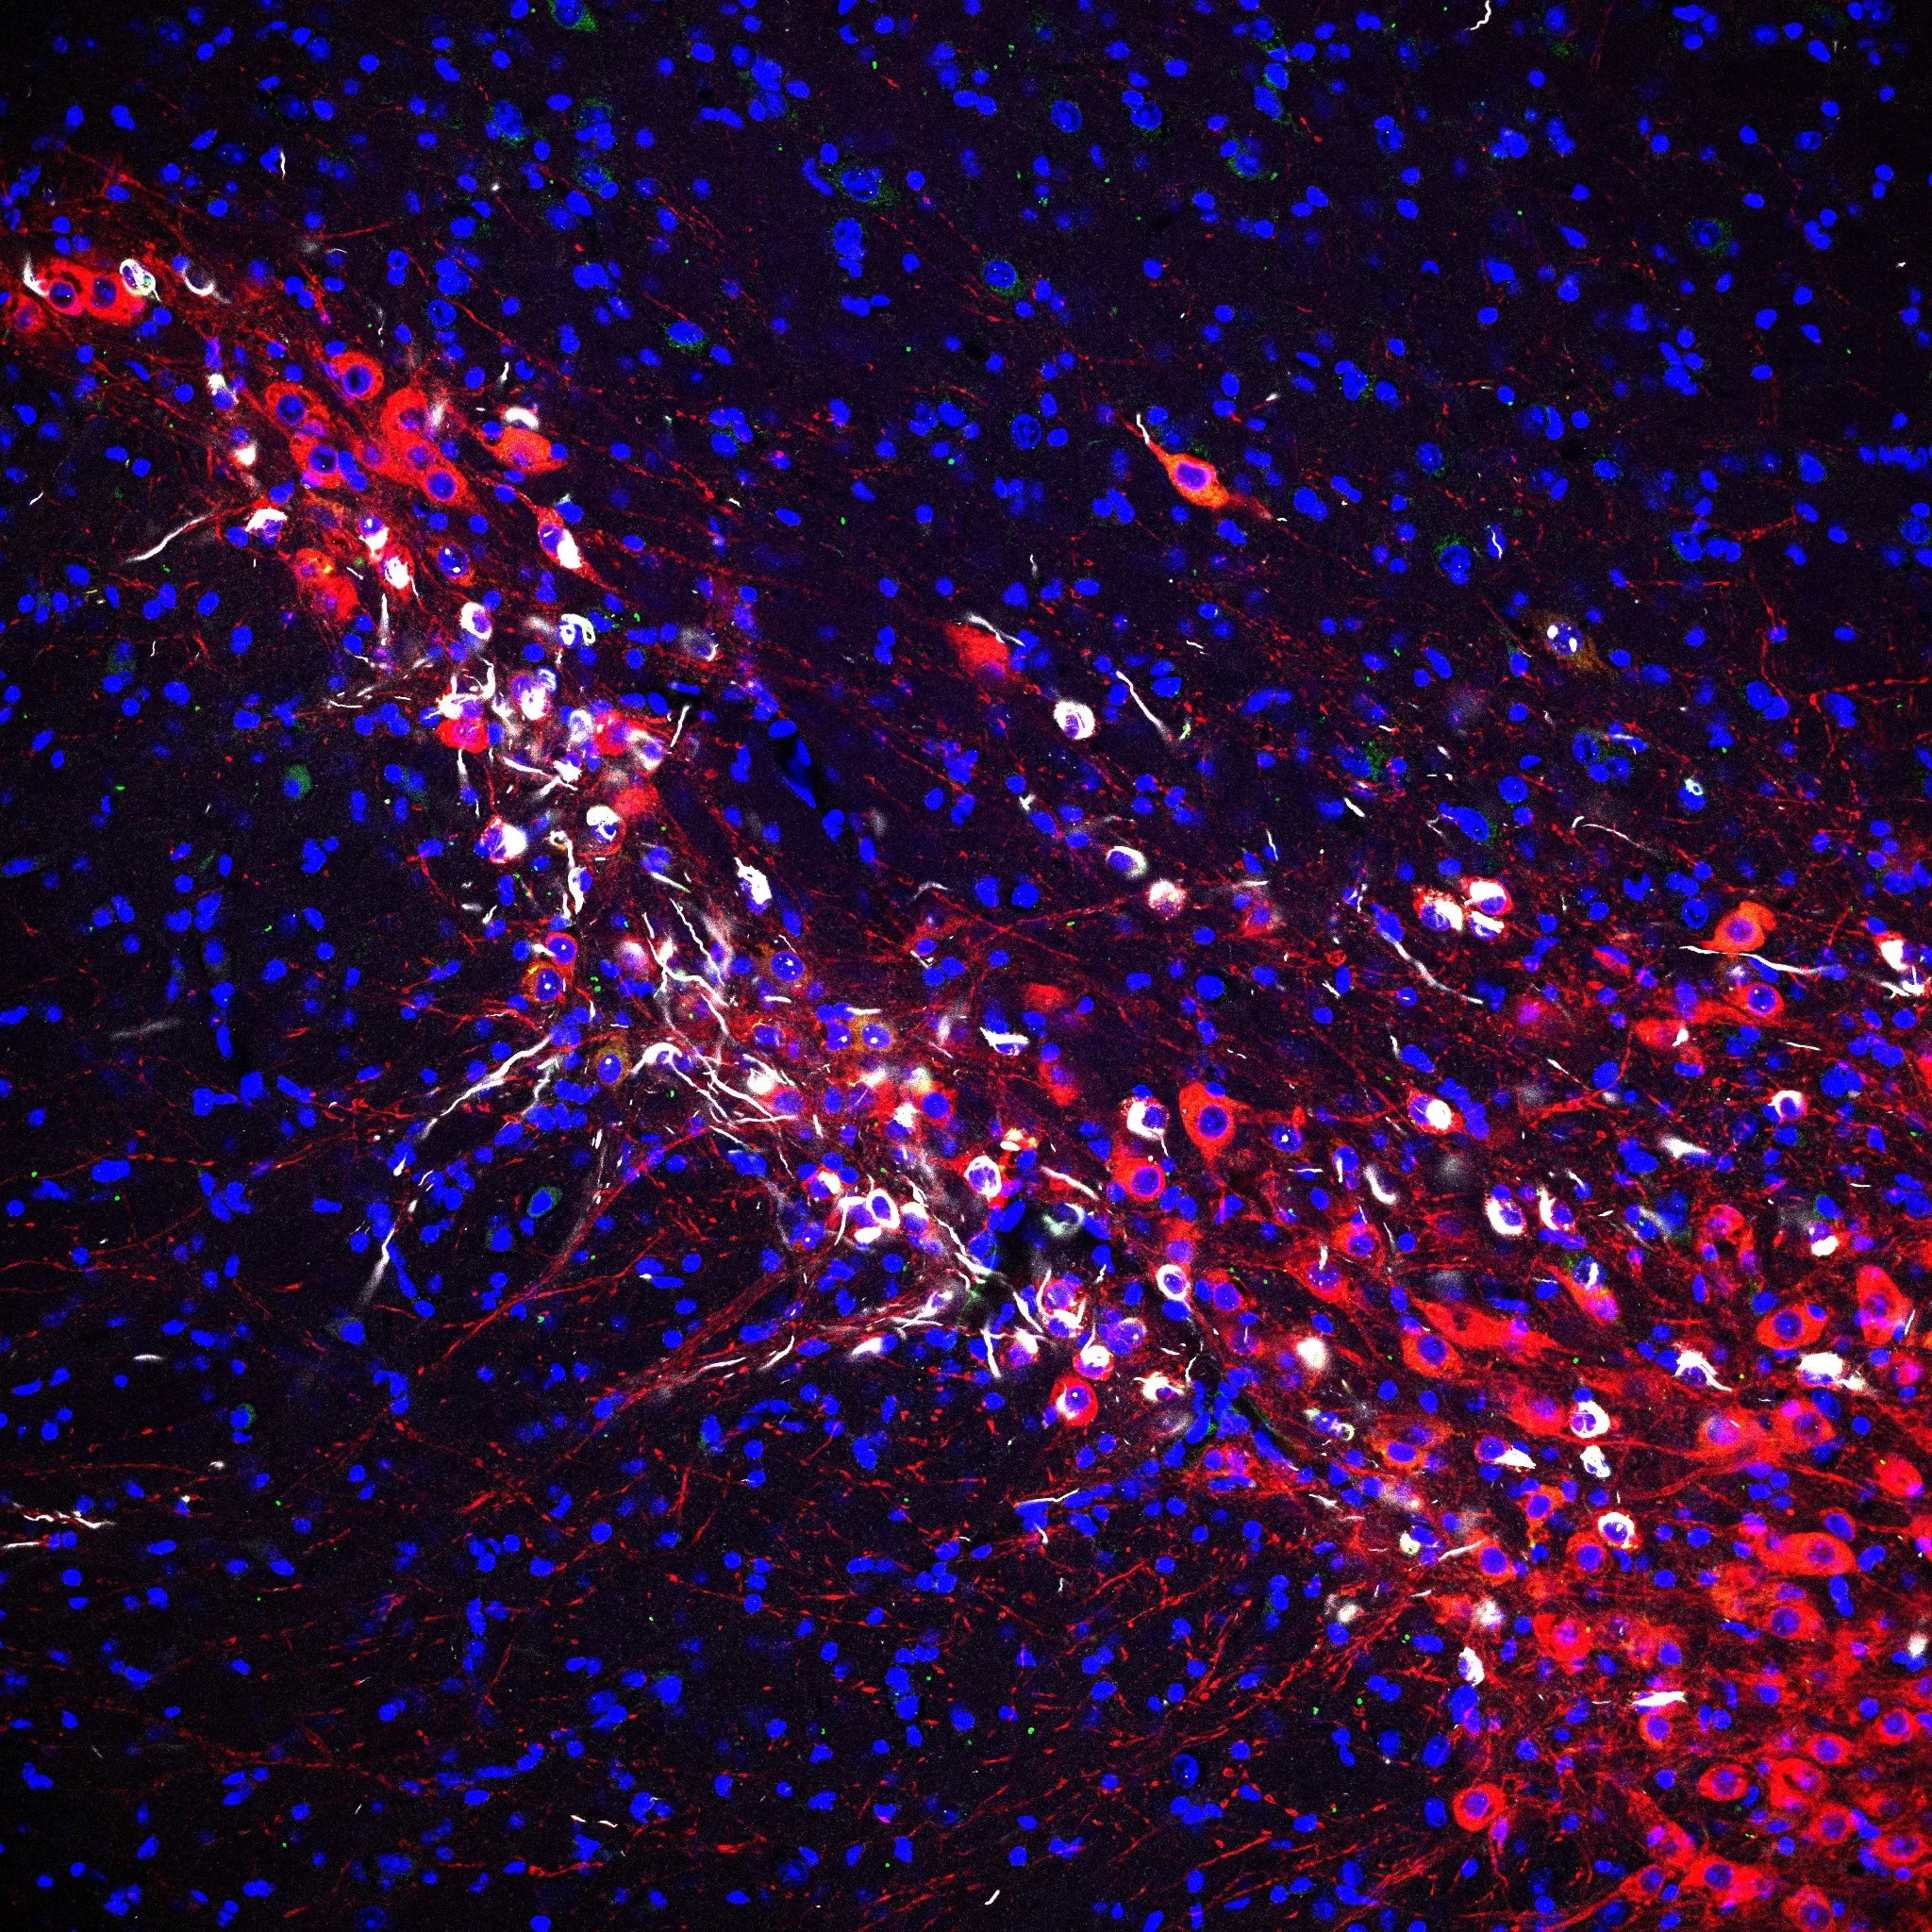

Parkinson’s disease is the most prevalent neurodegenerative movement disorder affecting millions of people worldwide. Neuropathologically, Parkinson’s disease is characterized by widespread loss of certain vulnerable neuronal populations, especially dopaminergic substantia nigra neurons, and formation of intraneuronal eosinophilic inclusions which stain positive for α-synuclein and are termed Lewy pathology.

Manifesting α-synuclein pathology (white) in dopaminergic substantia nigra neurons (red).

Intracellular aggregation of the small protein α-synuclein is a hallmark of Parkinson’s disease and thought to be responsible for the progressive loss of neurons. By combining up-to-date biosensors with two-photon-laser-scanning-microscopy we investigate how Lewy pathology causes neurons to die in Parkinson’s disease.